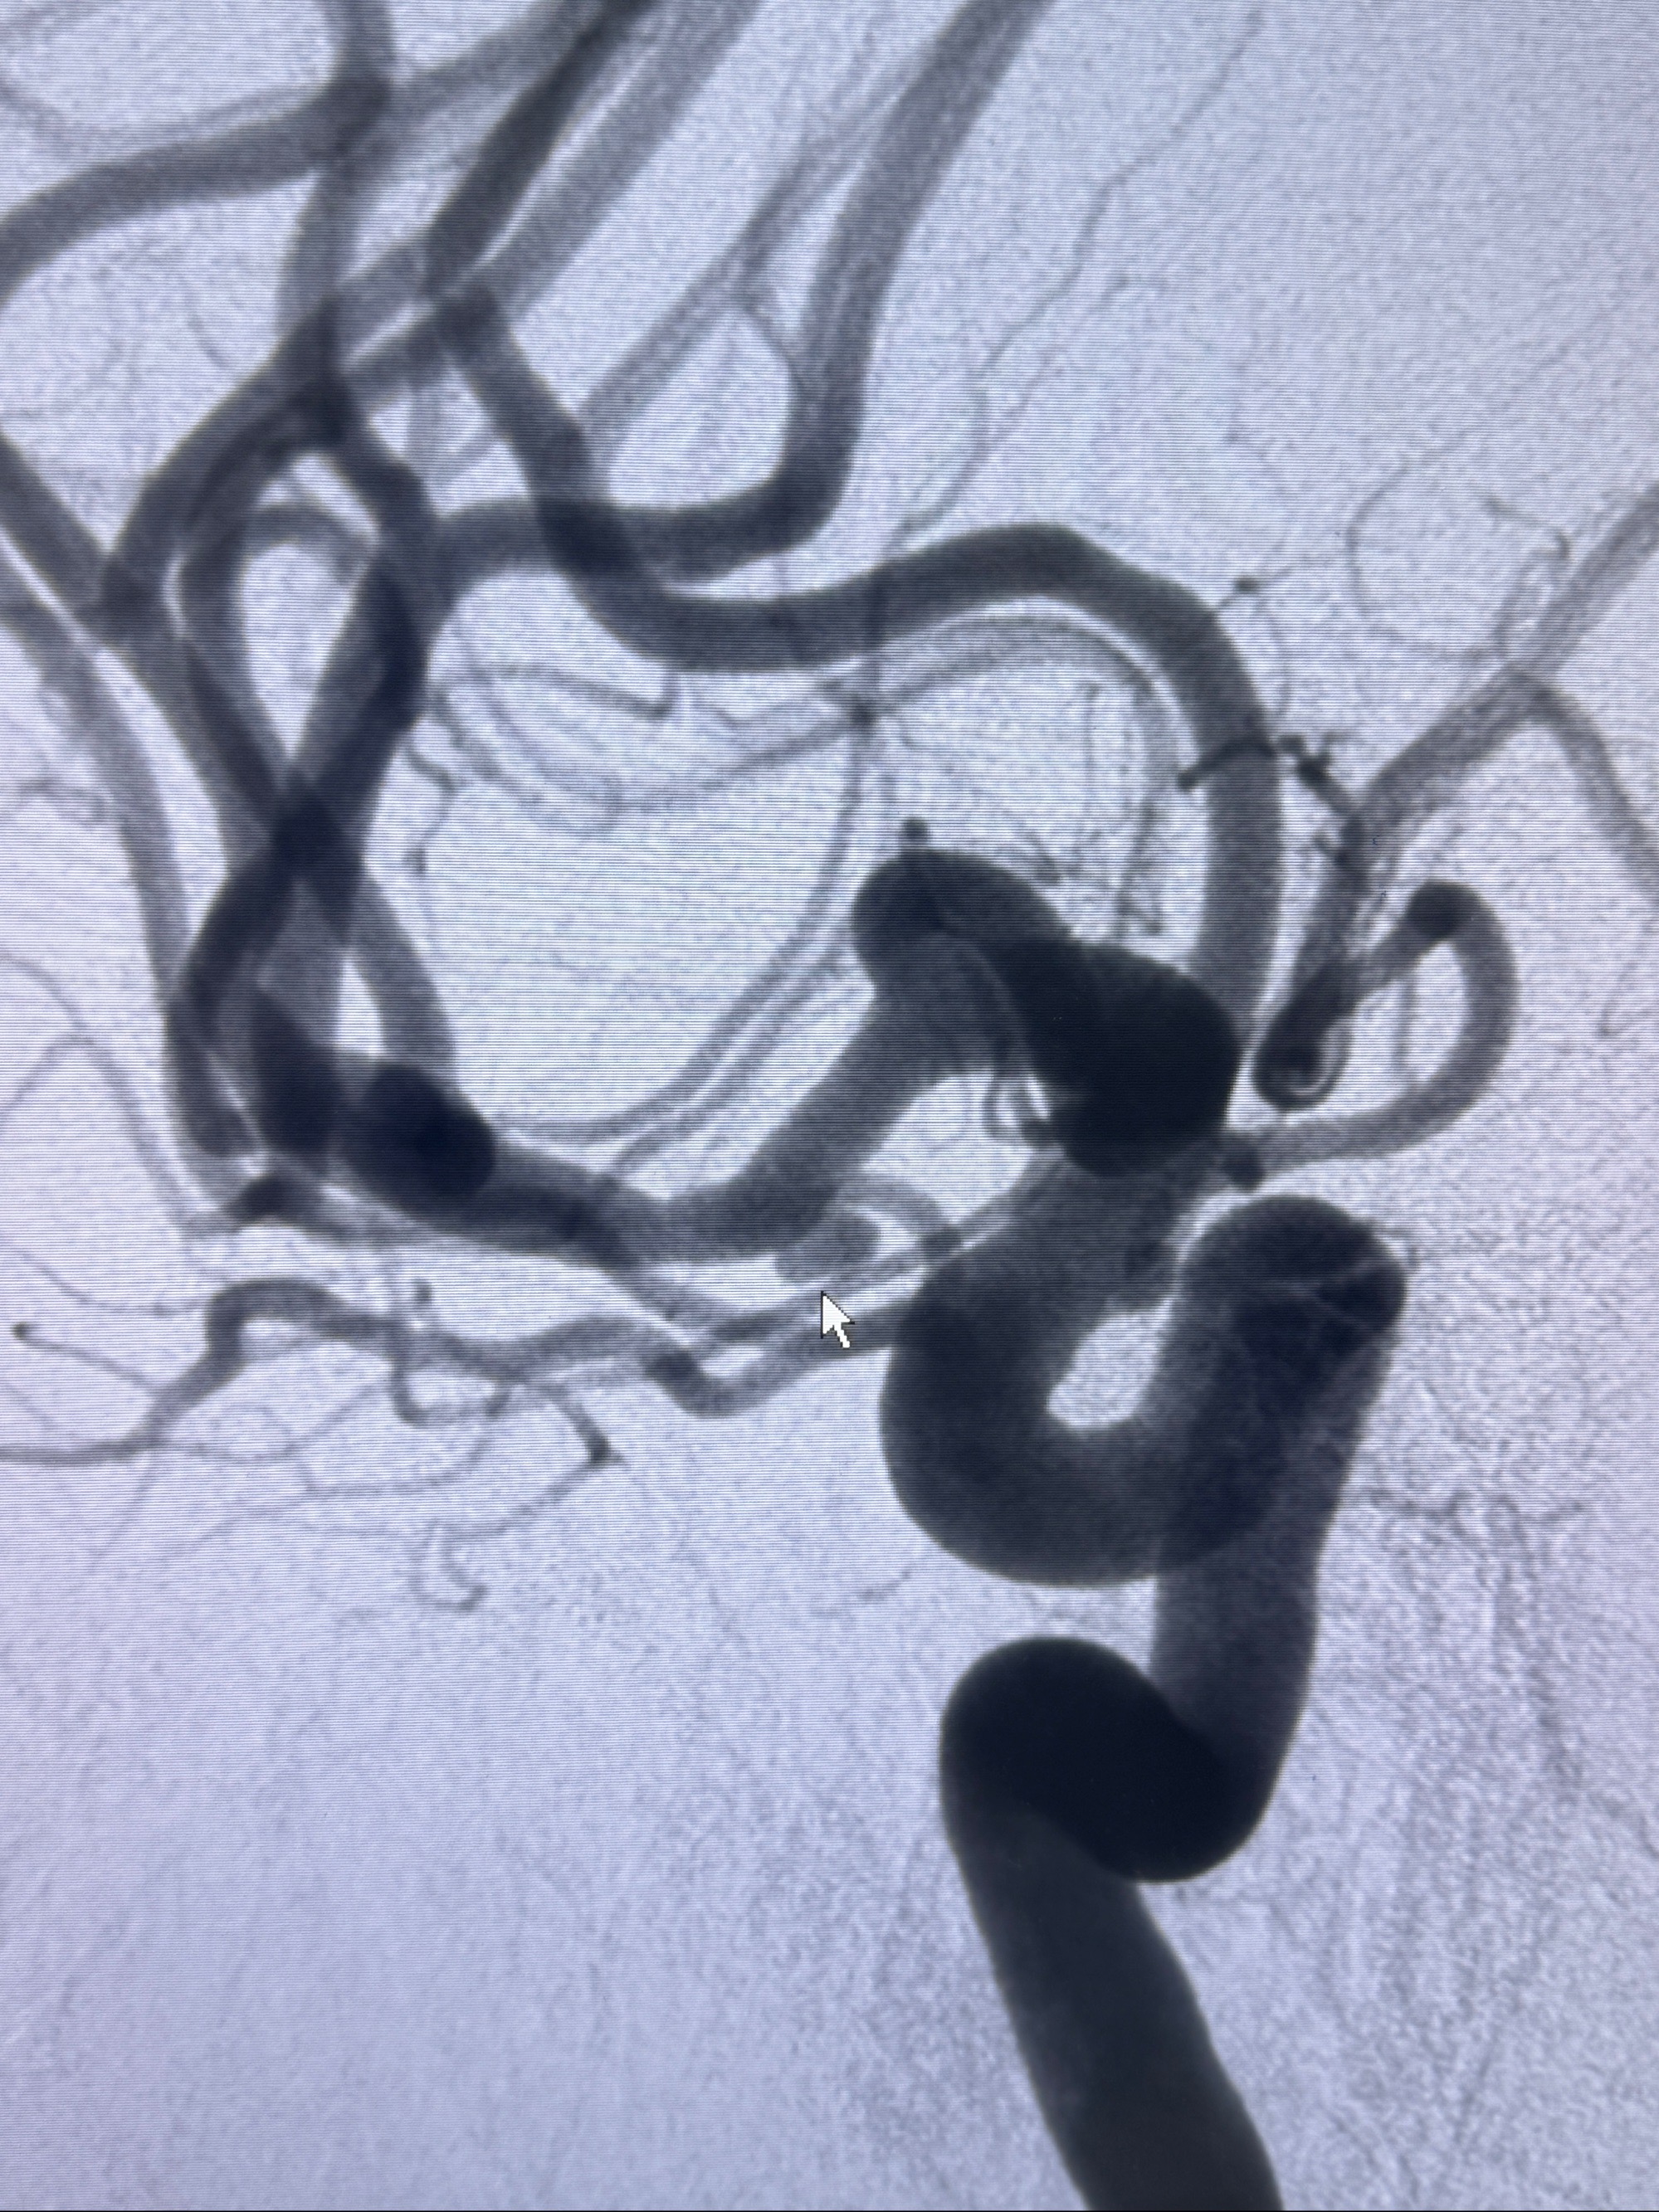

2023-11-24DSA:右侧大脑中动脉下干起始部动脉瘤,约2.3*2.5mm,形态规则

2023-12-04全麻下行支架辅助治疗

S-AB4-20mm